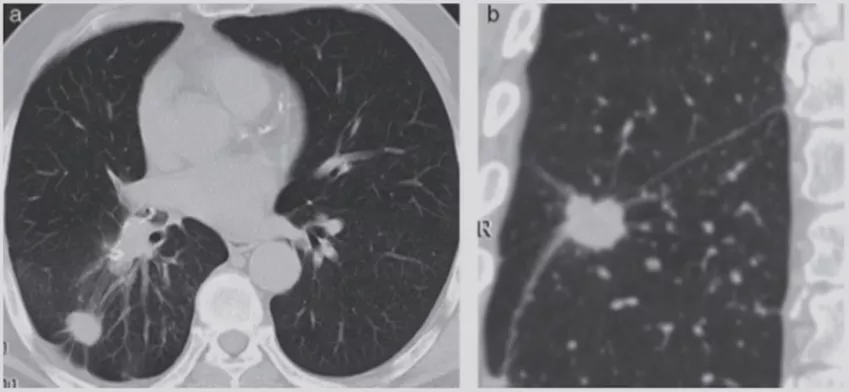

小细胞肺癌

小细胞肺癌以中央型多见,但是也有少数为周围型病灶。多为单个实性结节或肿块,可见分叶、毛刺、血管集束征、胸膜牵拉征。实际上我们很难从影像学上判断出小细胞肺癌的病理类型,往往是活检或者手术以后才能证实。如下图示,这属于I期的小细胞肺癌,进行手术的效果非常好。所以对于周围型小细胞肺癌,如果在结节很小的时候判断出来就做了手术,疗效非常好。我们知道小细胞肺癌是肺癌中治疗效果最差的,恶性程度是最高的。如果早期手术,仍然能够起到很好的效果。